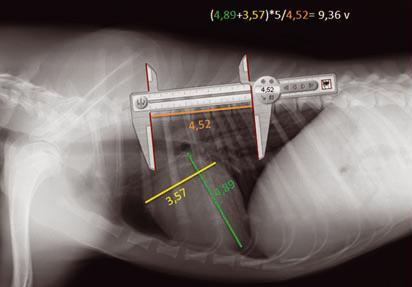

Vertebral Scale System to Measure Canine Heart Size in Radiographs. James Buchanan and Jorg Bücheler. JAVMA January 1995; 206(2): 194-199. Quote: "A method for measuring canine heart size in radiographs was developed on the basis that there is a good correlation between heart size and body length regardless of the conformation of the thorax. The lengths of the long and short axes of the heart of 100 clinically normal dogs were determined with calipers, and the dimensions were scaled against the length of vertebrae dorsal to the heart beginning with T4. The sum of the long and short axes of the heart expressed as vertebral heart size was 9.7 +/- 0.5 vertebrae. The differences between dogs with a wide or deep thorax, males and females, and right or left lateral recumbency were not significant. The caudal vena cava was 0.75 vertebrae +/- 0.13 in comparison to the length of the vertebra over the tracheal bifurcation. ... The major uses of the VHS method are in helping determine whether cardiomegaly exists in dogs with minimal radiographic changes and quantification of the progression of cardiomegaly over time in a glven dog."